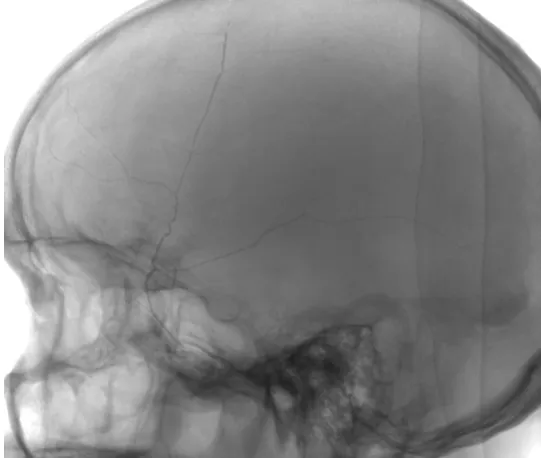

一个月前,83岁的陈阿公(化名)不小心摔了一跤,磕到了脑袋,但由于没有出现明显的头晕、头痛等症状,就一直没有到医院检查。可就在几天前,阿公的状况开始有点不对劲了,头闷闷的,有点痛,走路也没力气。家人赶紧把他送到温州医科大学附属第一医院急诊科就诊,急诊医生不敢大意,立刻安排阿公做了急诊头颅CT,检查结果提示:右侧慢性硬膜下血肿,这是颅内出血最为常见的类型之一,血肿量初步评估达到了三四十毫升。

▲ 慢性硬膜下血肿ct图